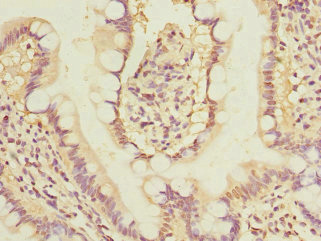

圖片:

應(yīng)用范圍:ELISA, IHC

Application Recommended Dilution IHC 1:20-1:200 -